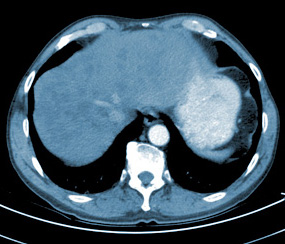

Voraussetzung für eine individuelle Behandlung ist die Kenntnis von Art, Natur und Stadium der vorliegenden Erkrankung. In der Diagnostik ist die Onkologie häufig auf Röntgenuntersuchungen angewiesen.

Beispiele oft verordneter Untersuchungen sind: konventionelle Röntgenaufnahmen, Computertomografien, Mammografien, Ultraschall-, PET- und Magnetresonanz-Untersuchungen oder Knochenszintigrafien.